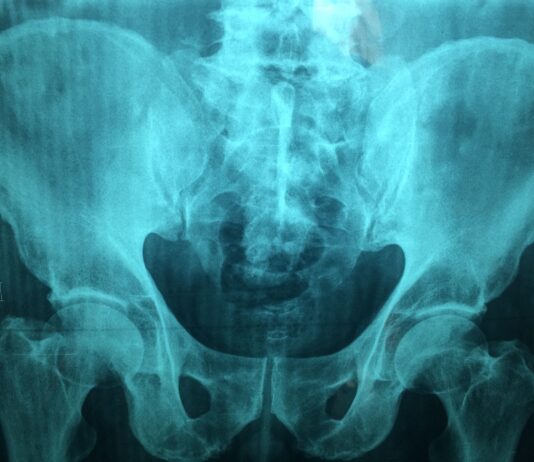

Stabilità dinamica e statica in pazienti con protesi post amputazione transfemorale

Uno dei principali esiti dell'amputazione transfemorale e del conseguente uso di una protesi è la riduzione dell'equilibrio, sia statico sia dinamico, con...